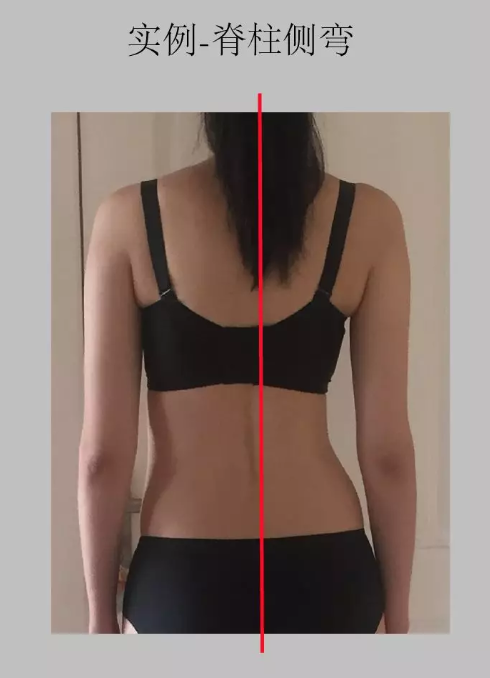

看下面这个站的歪歪的图,不用说,从后面看脊柱是歪的,或者两侧肩膀明显不一样高。

如果从背面看出现上图这一类,就一定需要找医生或者物理治疗师或者整脊师来寻求 专业 帮助,因为这一类成因比较复杂,有可能天生,有可能是 骨盆 有歪斜,旋转等问题。

③ 通过背面观察的体态问题

· 脊柱侧弯:观察躯干在背面观时,是否左右对称。